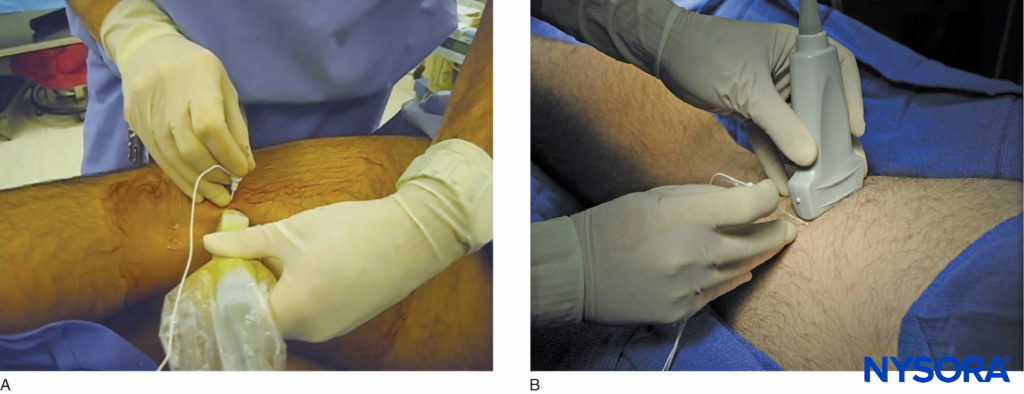

However, US guidance reduces the volume required for a reliable nerve block because the injection can be halted once adequate spread is observed. The most common approaches to the popliteal sciatic nerve block are the lateral approach, with the patient in the supine or lateral position, and the posterior approach in the prone or lateral position (Figure 2). While the patient position and needle path differ between the two approaches, the rest of the technique details are similar.

FIGURE 2. The posterior approach to the US-guided popliteal sciatic nerve block can be performed (A) with the patient in the lateral position, or (B) with the patient prone.

This nerve block is performed with the patient in the supine or lateral position. This can be accomplished either by resting the foot on an elevated footrest or flexing the knee while an assistant stabilizes the foot and ankle on the bed (Figure 6). If nerve stimulation is used, exposure of the calf and foot is required to observe motor responses.

FIGURE 6. Needle insertion technique to nerve block the sciatic nerve in the popliteal fossa using the lateral approach with the patient in the supine position.

LANDMARKS AND PATIENT POSITIONING: POSTERIOR APPROACH

This nerve block is performed with the patient in the prone or lateral position (Figure 2). A small footrest is useful to facilitate identification of a motor response if nerve stimulation is used. A footrest also relaxes the hamstring tendons, making transducer placement and manipulation easier.